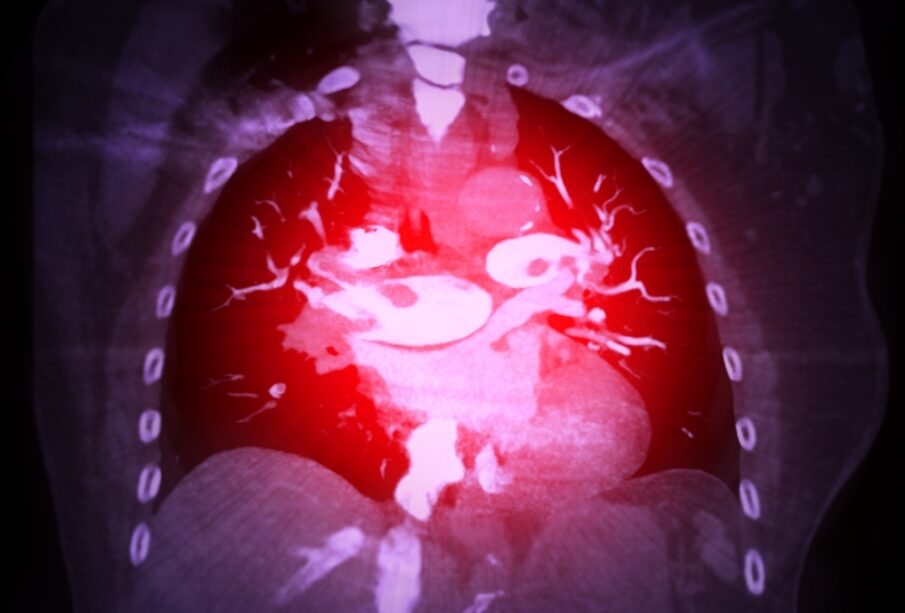

Plaučių embolija – tai rimta būklė, kai į plaučių arteriją ar jos šakas patenka ir ją užkemša svetimkūnis. Dažniausiai tai būna kraujo krešulys, tačiau retais atvejais užsikimšimą gali sukelti ir kitos medžiagos, pavyzdžiui, riebalai, oras, navikinės ląstelės ar net vaisiaus vandenys.

Didžiausia plaučių embolijos priežastis – nuo kraujagyslės sienelės atplyšęs giliosios venos trombas (DVT). Paprastai toks trombas susiformuoja stambiosiose rankų arba kojų venose, o vėliau nukeliauja į širdį ir iš ten – į plaučių arteriją, kur ją užkemša. Kadangi plaučių embolija ir giliųjų venų trombozė yra itin glaudžiai susijusios, diagnozavus vieną iš šių būklių paprastai tiriama ir kita.